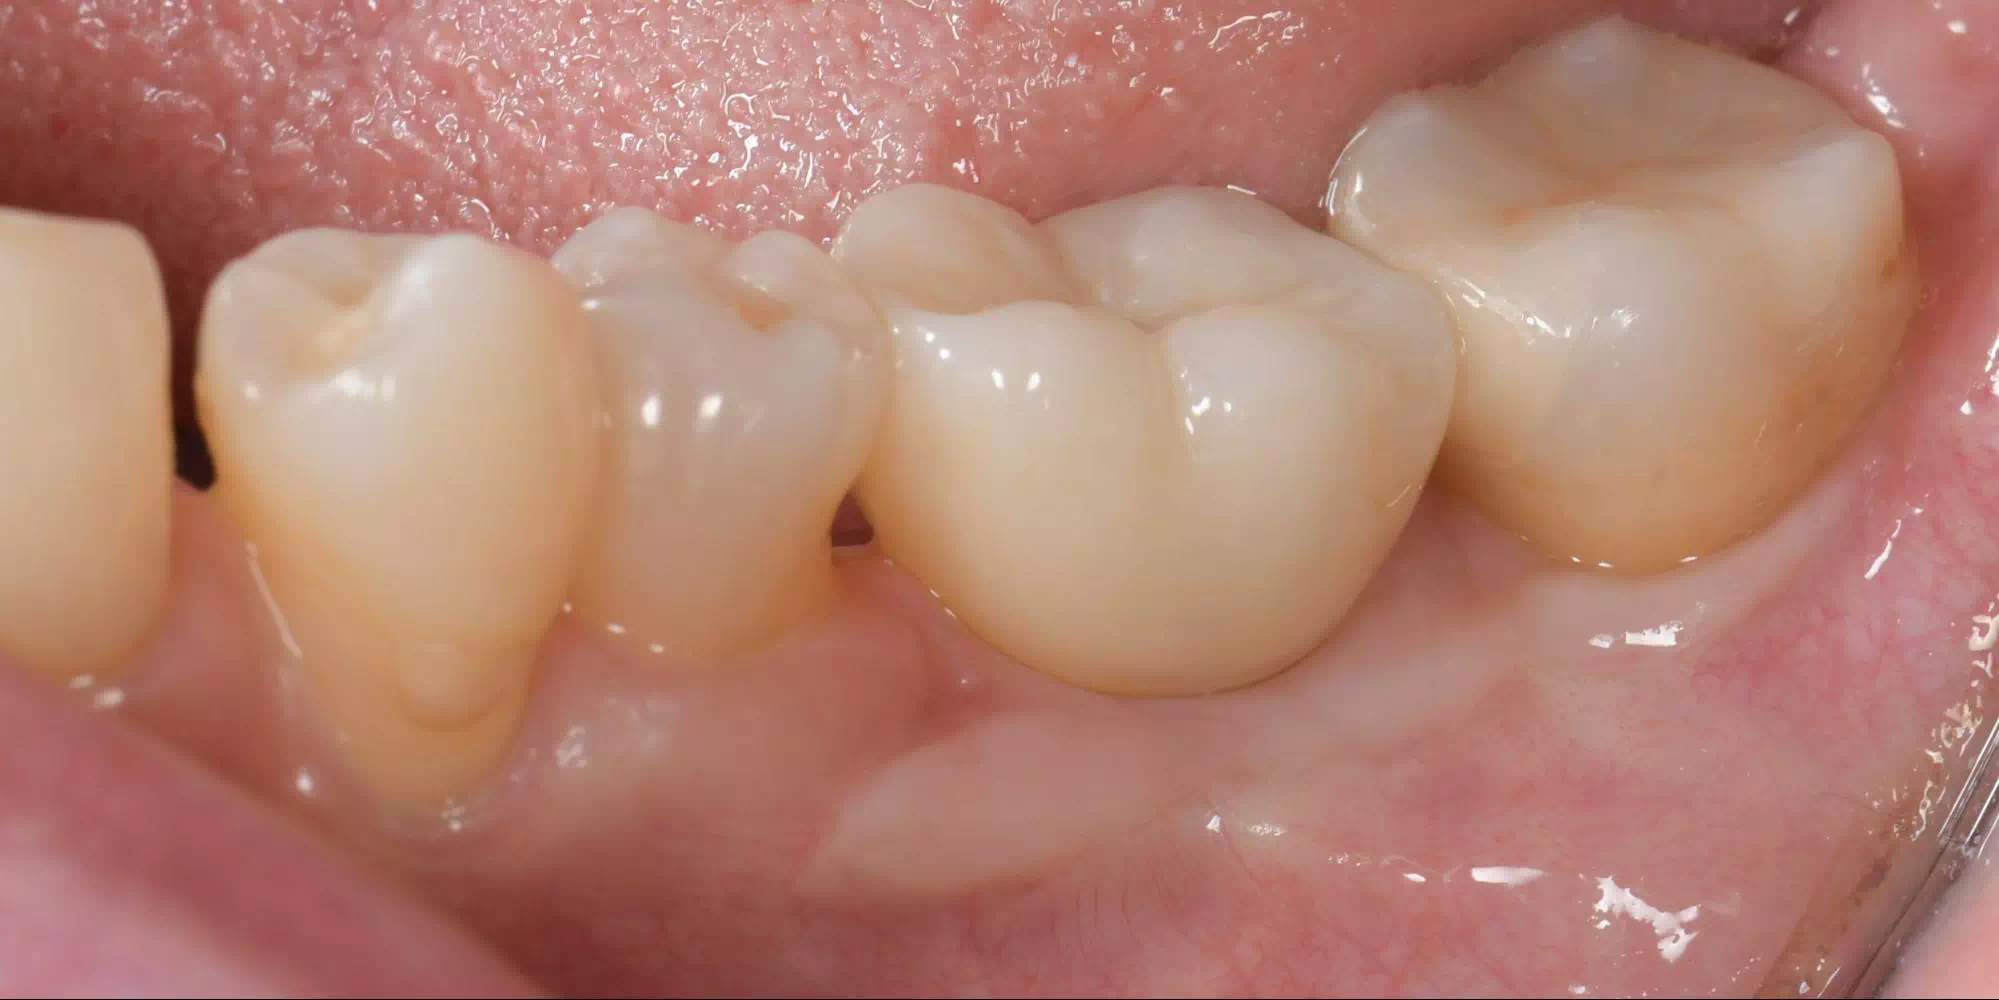

CASE HOME CASE 2025/10/21 抜歯即時埋入・即時荷重 症例 2025/10/21 GBR① 2025/10/21 インプラント 症例② 2025/10/21 インプラント 症例① 2025/10/21 矯正歯科 症例 2025/10/21 審美歯科 症例② 2025/10/21 審美歯科 症例① 2025/10/21 ガミースマイル 症例 2025/10/21 歯肉再生 症例② 2025/10/21 歯肉再生 症例① 2025/10/21 虫歯症例